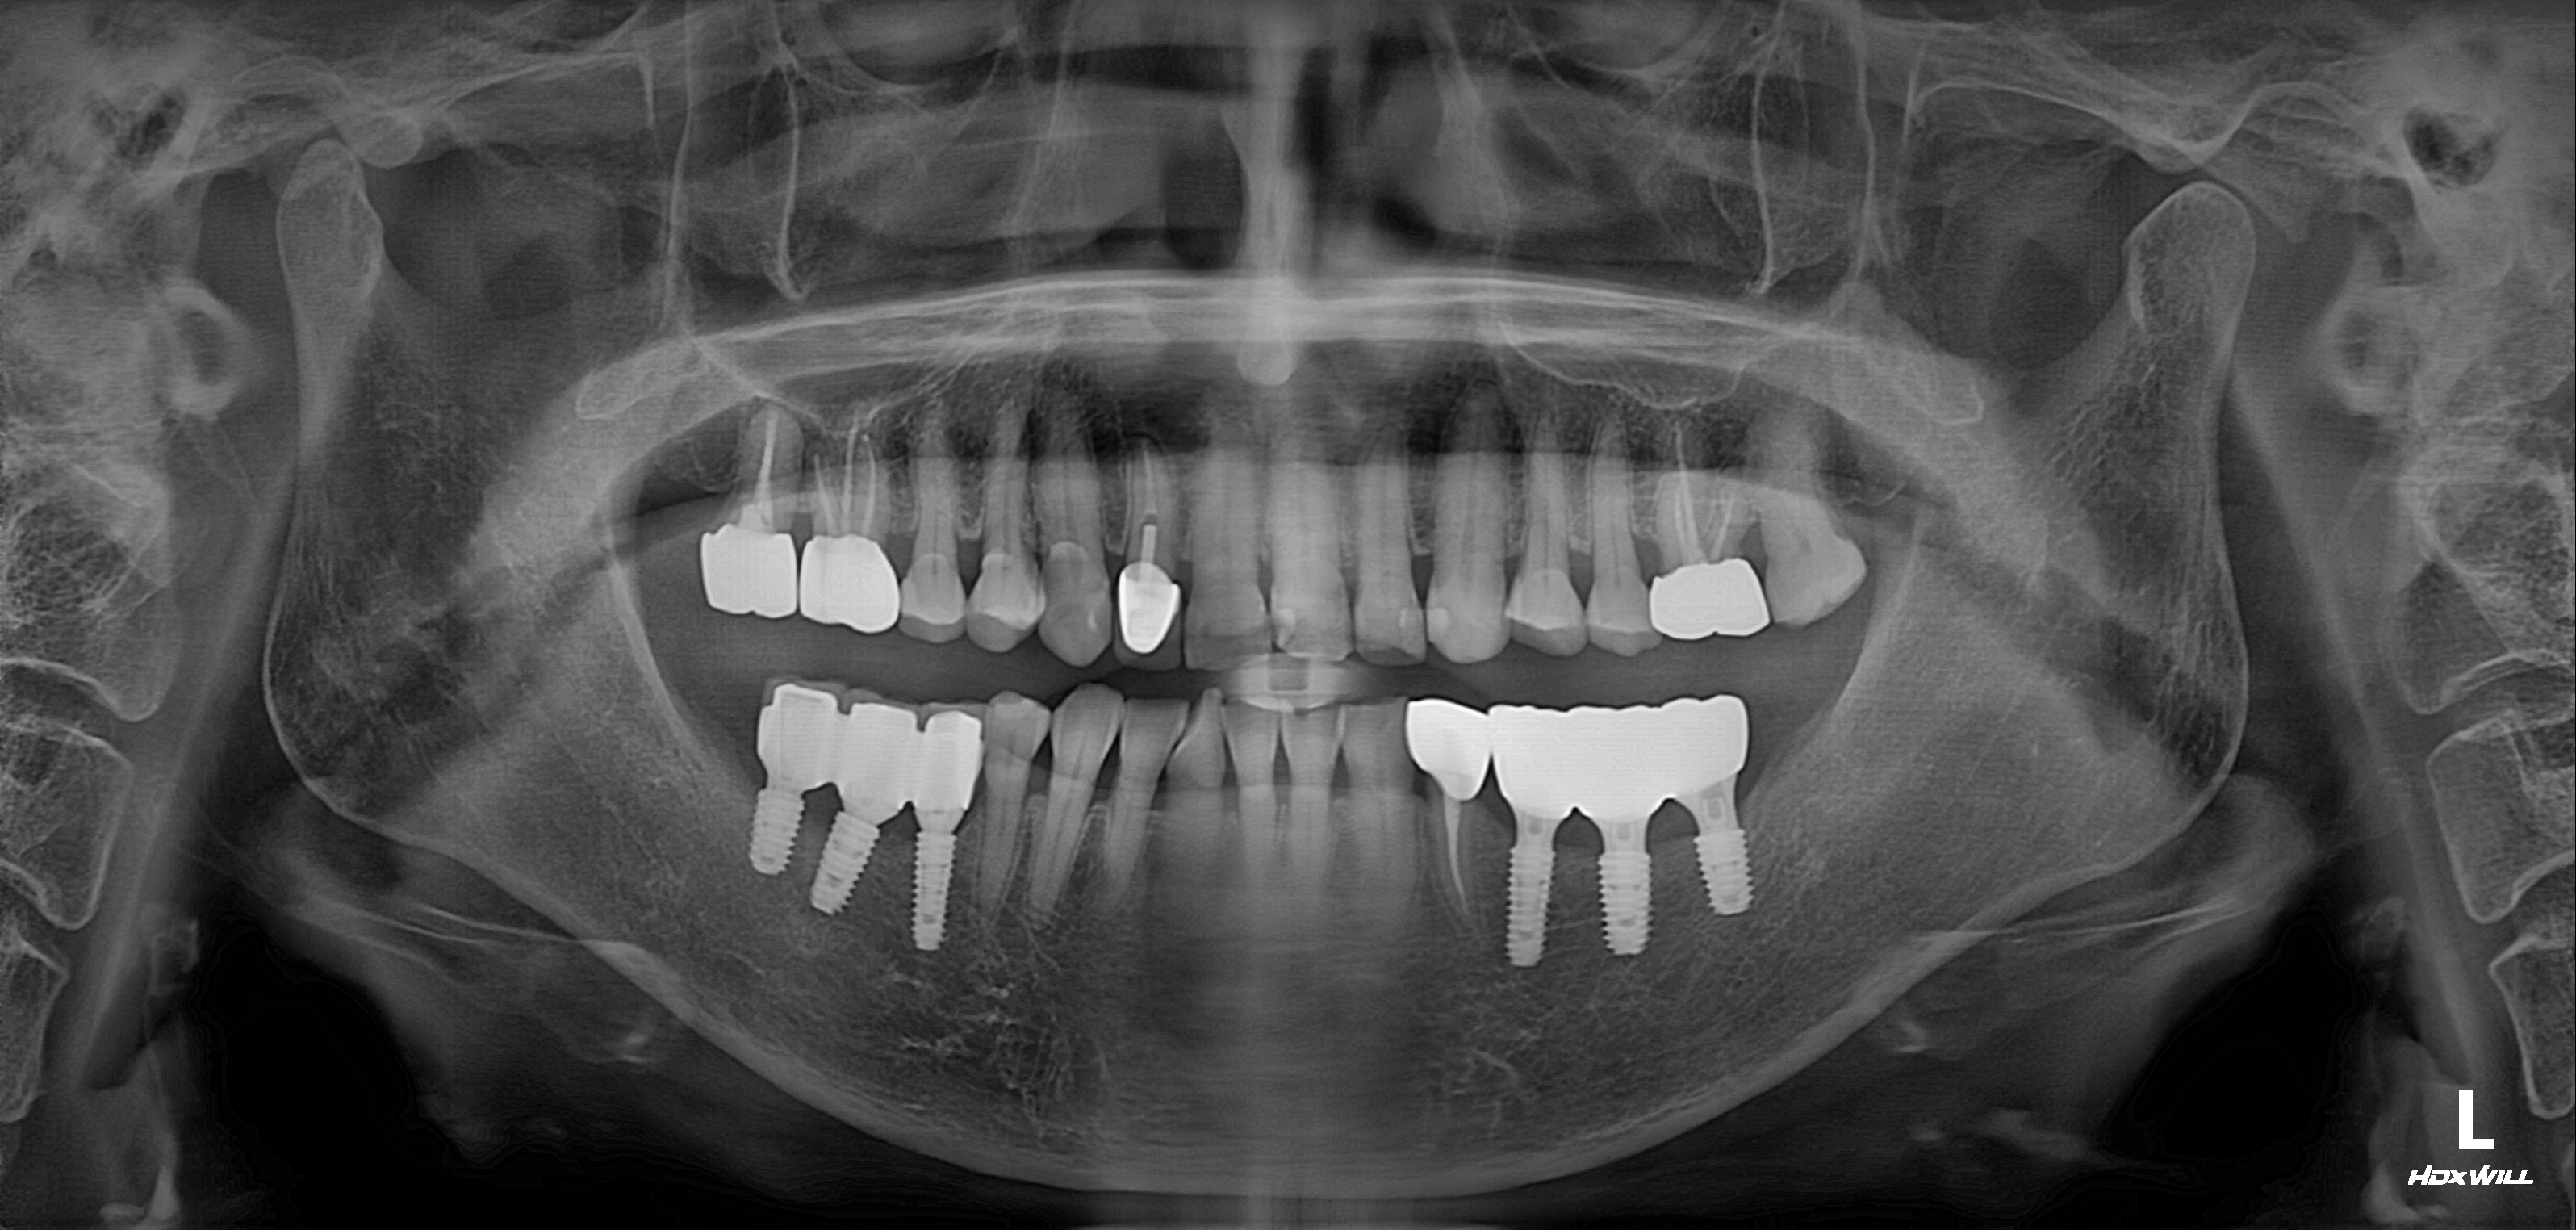

수술 전

수술 후

구치부 임플란트 식립사례

전후사진